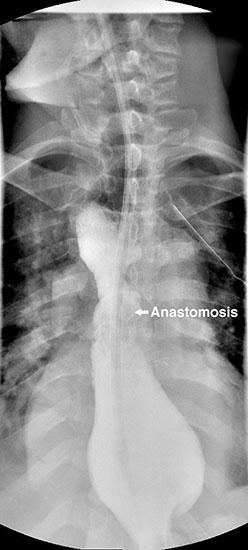

A 49 year old male presented to our institution with significant dysphagia and a 40 lb. weight loss secondary to a distal esophageal stricture. The patient had ingested lye 4 years previously and required partial gastrectomy, gastrojejunostomy, and partial colectomy at an outside institution at that time. His symptoms of dysphagia had progressively worsened despite repeated dilations and placement of an esophageal stent (Figure 1). Surgical reconstruction was therefore felt to be indicated. Preoperative computerized tomography angiogram did not clearly display the blood supply to the stomach, but did show that the colonic vasculature was adequate for use as a conduit if needed.

Figure 4. Postoperative barium swallow demonstrating free flow through the anastomosis with no residual stricture.

The patient had an uncomplicated course. His nasogastric tube was removed on postoperative day five. A water-soluble esophageal swallow study on postoperative day six demonstrated normal flow of contrast through the anastomosis and stomach into the jejunum, with no evidence of leak or obstruction (Figure 4). The patient was discharged to home on regular diet on postoperative day eleven. Pathologic analysis of the specimen revealed multiple strictures within the esophagus, to a diameter as narrow as 5 mm, and no evidence of malignancy. The patient had complete resolution of his dysphagia on 9 month follow-up and was returning to his baseline weight.